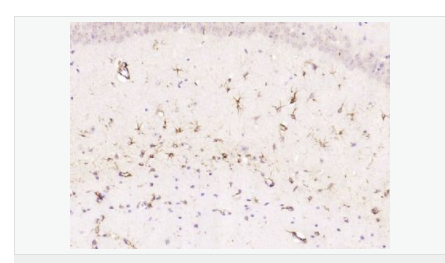

| 產(chǎn)品應(yīng)用 | WB=1:500-2000 ELISA=1:5000-10000 IHC-P=1:200-1000 IHC-F=1:200-1000 Flow-Cyt=1μg/Test ICC=1:100 IF=1:200-800 (石蠟切片需做抗原修復(fù)) not yet tested in other applications. optimal dilutions/concentrations should be determined by the end user. |

| 產(chǎn)品介紹 | This gene encodes one of the major intermediate filament proteins of mature astrocytes. It is used as a marker to distinguish astrocytes from other glial cells during development. Mutations in this gene cause Alexander disease, a rare disorder of astrocytes in the central nervous system. Alternative splicing results in multiple transcript variants encoding distinct isoforms. [provided by RefSeq, Oct 2008] Function: GFAP, a class-III intermediate filament, is a cell-specific marker that, during the development of the central nervous system, distinguishes astrocytes from other glial cells. Subunit: Interacts with SYNM. Isoform 3 interacts with PSEN1 (via N-terminus). Subcellular Location: Cytoplasm. Note=Associated with intermediate filaments. Tissue Specificity: Expressed in cells lacking fibronectin. Post-translational modifications: Phosphorylated by PKN1. DISEASE: Defects in GFAP are a cause of Alexander disease (ALEXD) [MIM:203450]. Alexander disease is a rare disorder of the central nervous system. It is a progressive leukoencephalopathy whose hallmark is the widespread accumulation of Rosenthal fibers which are cytoplasmic inclusions in astrocytes. The most common form affects infants and young children, and is characterized by progressive failure of central myelination, usually leading to death usually within the first decade. Infants with Alexander disease develop a leukoencephalopathy with macrocephaly, seizures, and psychomotor retardation. Patients with juvenile or adult forms typically experience ataxia, bulbar signs and spasticity, and a more slowly progressive course. Similarity: Belongs to the intermediate filament family. SWISS: P14136 Gene ID: 2670 Database links: Entrez Gene: 2670 Human Entrez Gene: 14580 Mouse Omim: 137780 Human SwissProt: P14136 Human SwissProt: P03995 Mouse Important Note: This product as supplied is intended for research use only, not for use in human, therapeutic or diagnostic applications. 星形膠質(zhì)細(xì)胞標(biāo)志物 (Astrocyte Marker) GFAP是一個56kDa的中間絲蛋白(intermediate filament,IF),在中樞神經(jīng)系統(tǒng)發(fā)育期是一個特異性的標(biāo)志物,以區(qū)別星形細(xì)胞和其它膠質(zhì)細(xì)胞。GFAP表達(dá)在皮層和海馬,急、慢性皮質(zhì)酮治療時表達(dá)減少。 GFAP可以和人、大鼠、小鼠的GFAP反應(yīng),在正常和腫瘤性的星形膠質(zhì)細(xì)胞陽性表達(dá),而神經(jīng)節(jié)細(xì)胞、神經(jīng)元、成纖維細(xì)胞、少突膠質(zhì)細(xì)胞和這些細(xì)胞來源的腫瘤細(xì)胞陰性表達(dá),主要用于星形膠質(zhì)瘤等中樞神經(jīng)系統(tǒng)腫瘤的診斷和鑒別診斷,GFAP的缺乏可導(dǎo)致AD病。 |